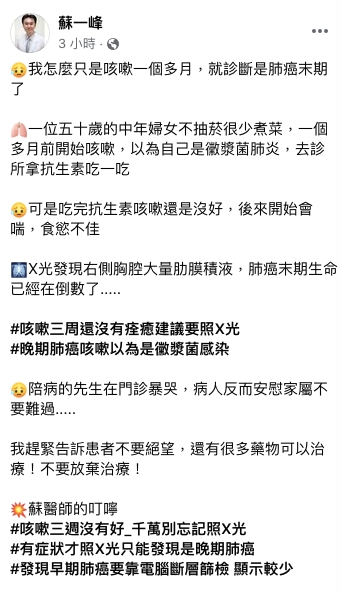

疾病看不到也摸不到,就喜歡無預警找上來!胸腔暨重症專科指導醫師蘇一峰今天 (6) 在臉書以「我怎麼只是咳嗽一個多月,就診斷是肺癌末期了」為題,分享一段令人鼻酸的案例。

蘇一峰指出,有名50歲的中年婦女,平時不抽菸也很少煮菜,一個多月前開始咳嗽,以為是黴漿菌肺炎,就去診所拿抗生素吃,可是吃完抗生素咳嗽還是沒好,後來開始會喘、食慾不佳,一照X光發現,右側胸腔大量肋膜積液,「肺癌末期生命已經在倒數了……」

蘇一峰表示,陪診的丈夫聽到後,忍不住暴哭,病患反而安慰先生不要難過。蘇醫師趕緊安慰「不要絕望,還有很多藥物可以治療!不要放棄治療!」最後,他強調,早期肺癌可以靠電腦斷層篩檢,若「咳嗽三週沒有好,千萬別忘記照X光」,有症狀才詳查的話,通常已經是晚期。